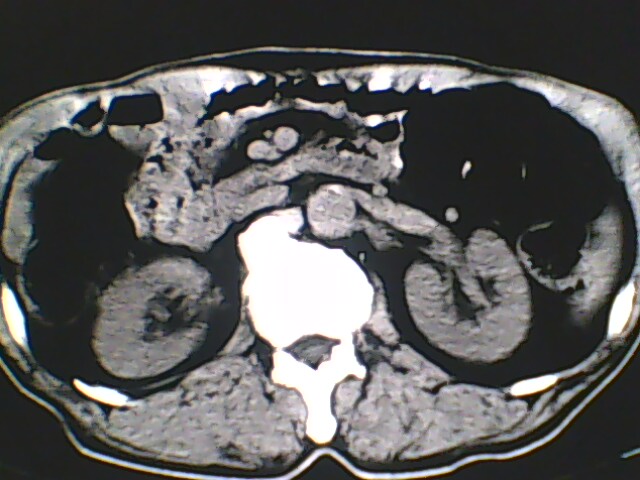

男,56岁,高血压,临床怀疑肾上腺问题,肝脏怎么那么高啊?能描述一下么?

右侧膈膨升,间位结肠,胸腰椎退行性骨关节病,右侧肾上腺可疑增生(图像颗粒太粗,窗太窄,不好看)。

支持 右侧膈膨升,间位结肠;胸腰椎退行性骨关节病;双侧肾上腺可疑增生。